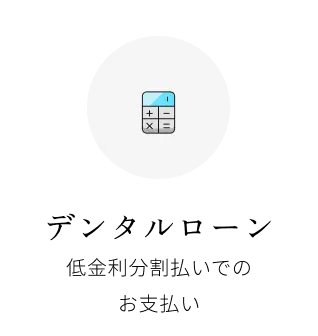

人工歯根療法とも言われ、歯を支える顎骨部分にボルトを埋め込み、人工の歯を被せる治療方法です。メリットとしては、ご自身の歯と同じような感覚で噛めるようになることが挙げられます。審美性が高いため、美しく仕上がることもインプラントの特長です。留意点としては、治療期間が長く、保険適用外のため治療費は高額になります。

埋入手術

治療計画に従い、インプラントを顎骨に埋める手術を行います。骨造成が必要な場合、まずは骨を作ってインプラントを埋め込む2回法を取ります。

人工歯の装着

インプラントと顎骨が結合しましたら、アバットメントや人工歯を装着します。人工歯は患者様の口腔内に合うように、機能面や審美面にこだわって作製いたします。